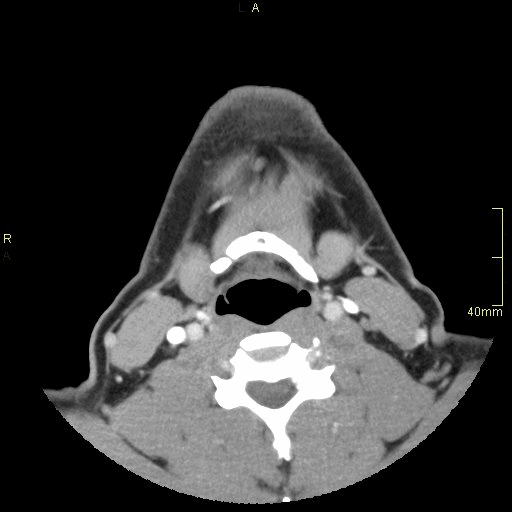

CT Facial Bones/Sinuses Contrast- Soft Tissue window (axial)

CT Facial Bones/Sinuses Contrast- Bone window (axial)